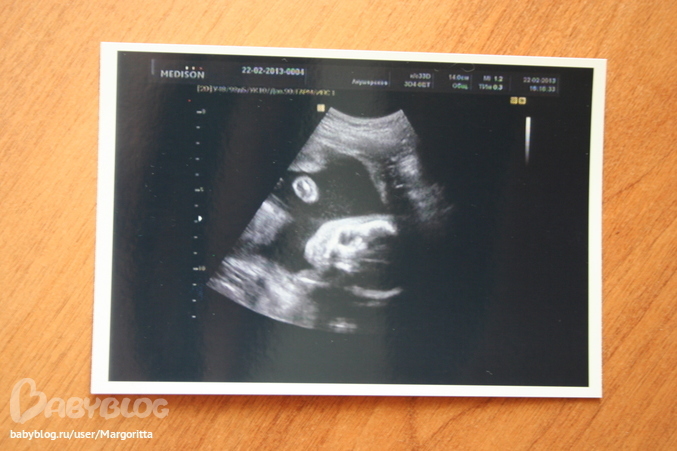

УЗИ, КТГ, доплерходили мы с будущим папой на второе узи и ..... у нас будет сыночек)))))

врач сказала, что все у нас хорошо. малыш крупный, опережает по размерам аккушерский срок почти на неделю. помохал нам ручкой и почесался)))

сделали еще доплер - там тоже все хорошо. так что растет у нас богатырь))) 480 грамм, 155 ударов сердца в минуту.

это фотка его личика))))